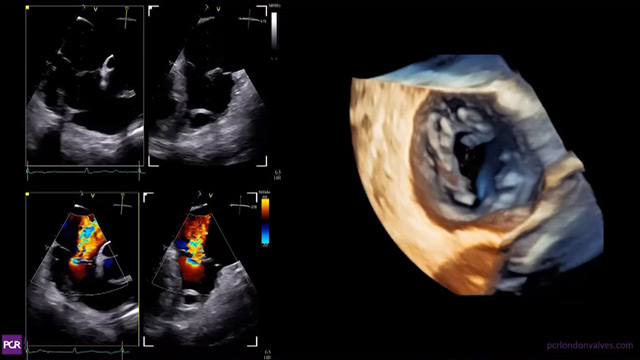

Mitral paravalvular leak closure: procedural planning and step-by-step performance

17 Nov 2025 – From PCR London Valves 2025

This session provides an expert overview of mitral paravalvular leak closure, emphasizing critical clinical and anatomical selection criteria. It covers essential pre-procedural imaging and planning strategies, complemented by an educational recorded case and a review of immediate and long-term procedural outcomes.